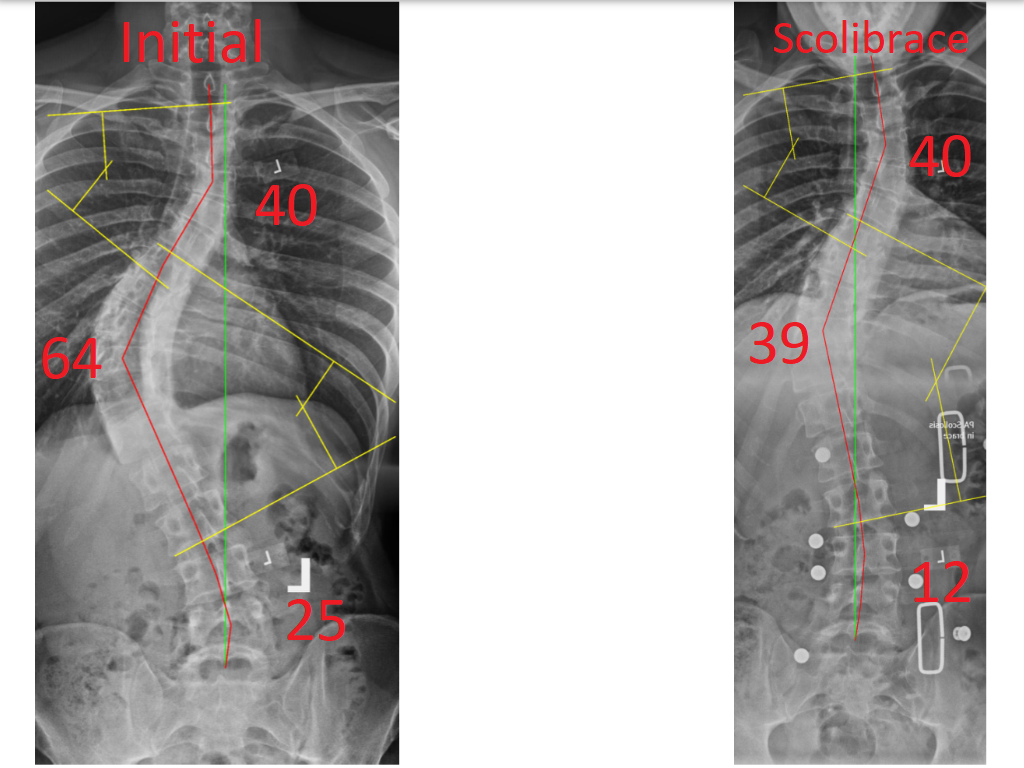

Episode 136 Scoliosis Degrees of Curvature